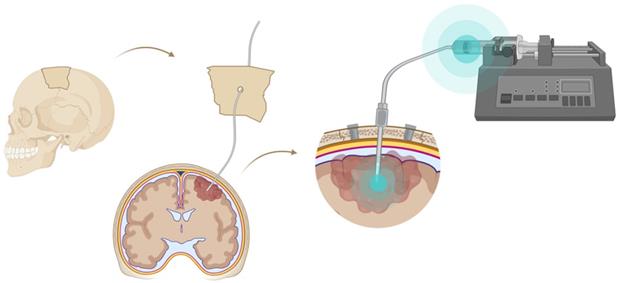

Figure 4

Convection enhanced delivery (CED) of a radiopharmaceutical. CED is a strategy whereby a drug is delivered directly into the tumor parenchyma via implanted catheters. Catheters are coupled with a pump to provide continuous positive-pressure microinfusion. Unlike systemic therapy, CED bypasses the blood-brain barrier (BBB) therefore making drug distribution relatively independent of its molecular charge and size [129].

A very successful strategy to bypass the BBB for GB TRT is loco-regional compound injection or convection enhanced delivery (CED). This is possible because 95% of GBs manifest as a unifocal lesion that recurs within a 2 cm margin at the primary site [105]. Most clinical RIT studies for malignant gliomas were performed via local administration [104,125,126]. Human studies using locoregional administration also showed promise in terms of tumour cell incorporation of AE-emitters [127]. In a clinical study by Krolicki et al., local injection of [213Bi]Bi-DOTA-SP was successfully performed 2-4 weeks after stereotactic implantation [105]. This group recommends an injection of corticosteroids and antiepileptic drugs thirty minutes before administration and up to 3 mL of injection volume. Co-injection of an imaging and therapeutic radionuclide (e.g. [68Ga]Ga-DOTA-SP combined with either [213Bi]Bi-DOTA-SP or [225Ac]Ac-DOTA-SP) enabled its distribution in the tumour to be monitored and subsequently the radioactivity occurrence in the whole body [105]. For CED, a catheter system, stereotactically placed intratumourally or into the post-surgical cavity, employs a pump to provide continuous positive pressure for local drug delivery (ranging from 0.1 to 10 μl/min) (Figure 3 and Figure 4) instead of a bolus injection [128,129]. This was proved to be a safe and effective drug delivery method, reaching a higher concentration of the drug within the GB tumour, and lack of systemic toxicity. This is especially favourable for α-particle emitters with relatively short half-lifes, such as bismuth-213 (45 min) or astatine-211 (7.2 h), as most of the radioactive decay will occur within the relevant cavity before being distributed throughout the body via the systemic and lymphatic systems [130]. Clinical trials applying CED are highlighted in recent reviews [111,131,132]. It should be noted that pre-therapy PET or SPECT imaging following traditional IV tracer injection contributes little information regarding TRT agent distribution, if CED is applied. When the position of a critical lesion makes local application of CED impossible, brain delivery of radiopharmaceuticals can still be improved by different strategies. In addition to the transcellular lipophilic pathway, the use of BBB shuttles constitute an elegant strategy to target the brain, including receptor-mediated transcytosis (RMT), carrier-mediated transcytosis (CMT) or adsorptive-mediated transcytosis (AMT) (Figure 3) [118,133]. RMT is another elegant strategy for the delivery of macromolecular pharmaceuticals (up to 80 nm in diameter) in the treatment of GB. However, the widespread expression of these receptors in other tissues, the small dissociation rate and potential toxicity require careful consideration [5,118]. Alternatively, relevant strategies modifying the PK of radiopharmaceuticals were recently reported [134,135]. Chimeric cell-penetrating peptides (CPP) can hereby aid the transportation of drugs (also tumour targeting peptides) unable to pass the BBB, by conjugating it to a brain drug-targeting vector. This CPP complex can cross the BBB via transcytosis; Mendes et al. reviewed this aspect for applications for GB therapy (Figure 3) [5]. Multiple prodrug strategies have been employed to facilitate transport into the CNS for brain tumour visualization and treatment, for instance carrier/ligand-drug conjugates [102]. The brain drug-targeting vector can be an endogenous peptide, a modified protein, or a peptidomimetic mAb that undergoes RMT through the BBB on endogenous receptor systems. One such example is [111In]In-EGF-SPECT-imaging, using a radiolabeled peptide conjugated to the transferrin receptor (TfR) targeting mAb OX26, which has been shown to detect brain tumours without EGF transport [136]. The diagram in Figure 5 demonstrates other strategies to increase BBB penetration. A fractionated dose administration over time could be advantageous to accommodate changes in blood flow and reductions in interstitial pressure caused by tumour reduction (Figure 5 (3)) [137]. A physical approach is the combination of low-intensity focused ultrasound (FUS) pulses with circulating microbubbles, which enhanced brain tumor delivery of trastuzumab, improving survival in a rat glioma model (Figure 5 (4)) [118,133,138]. The issue of a limited BBB penetration of mAbs, due their molecular size and hydrophilicity, may be overcome by using smaller antibody fragments or engineered antibodies [139]. Other noteworthy delivery platforms shuttling antibodies to the brain (tumour) may include liposomes, nanoparticle-based systems, CPPs, and whole cell-based concepts, actively studied in GB [5,140-146]. This can be combined with a pre-targeting approach, i.e. the administration of a non-radiolabeled antibody first, allowing it to localise to solid tumour sites, followed by a subsequent administration of a small molecular weight, radioactive moiety with high affinity for the tumour reactive antibody [108]. This strategy was successful using a three step ytterium-90 labelled biotin-anti-tenascin-PRIT approach in glioma. However the significant immunogenicity of streptavidin may cause negative side effects [147-149]. An active targeting approach, such as the encapsulation in polymeric nanocarriers, can be used to optimise confinement of the radioactivity near the GB cells (including daughter atoms) (Figure 5 (6)) [5,14,150]. The latter resulted in positive pre-clinical results [150,151]. In clinical studies of high-grade gliomas (treated with liposomal doxorubicin plus RT and TMZ) limited therapeutic efficacy was evident [118,150-152]. Finally, it should be noted that translation of nanoparticle-mediated delivery systems to the clinic is time-consuming, costly, and difficult.